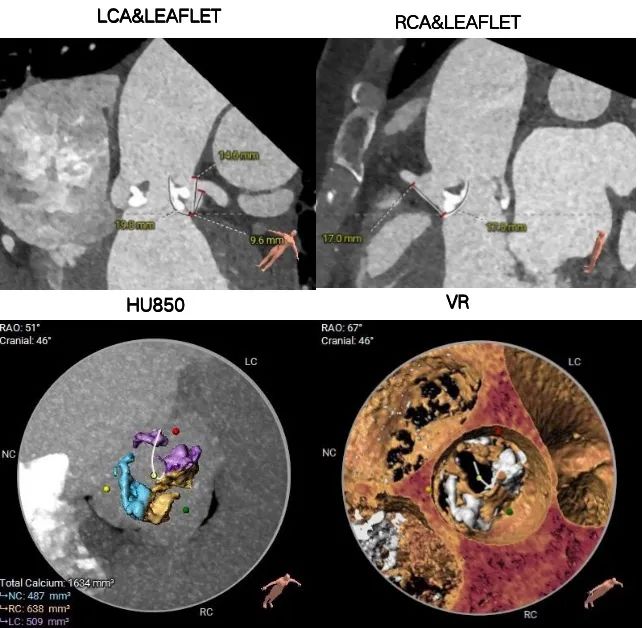

主动脉根部测量

冠脉及钙化数据测量

1.Type 2型二叶式主动脉瓣重度钙化,左窦和右窦、右窦和无窦瓣叶对合缘处存在钙化嵴,左室流出道呈敞口形态,瓣膜锚定难度适中,瓣膜植入受二叶瓣瓣叶及钙化挤压存在移位及少量偏多瓣周漏风险。

2.左冠脉开口高度偏低,左冠切线角度测量瓣叶大于LCA开口下缘到根部距离,结合瓦氏窦及STJ尺寸预估,冠脉风险增高。